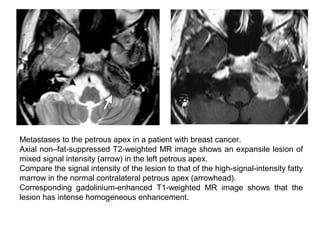

Metastases to the petrous apex in a patient with breast cancer.

Axial non–fat-suppressed T2-weighted MR image shows an expansile lesion of

mixed signal intensity (arrow) in the left petrous apex.

Compare the signal intensity of the lesion to that of the high-signal-intensity fatty

marrow in the normal contralateral petrous apex (arrowhead).

Corresponding gadolinium-enhanced T1-weighted MR image shows that the

lesion has intense homogeneous enhancement.